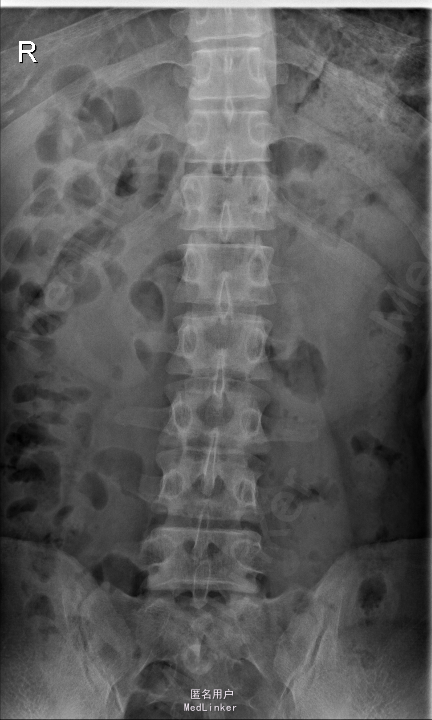

查体:腰部叩痛,腰部活动受限,左侧膝内侧、小腿外侧、内踝、足部感觉减退,右侧小腿、足背感觉减退,屈髋、伸膝、踝背伸肌肌力左侧4级,右侧4-5级,踇背伸、跖屈肌肌力左侧3-4级,右侧4级,双侧膝腱反射+,跟腱反射+,双侧巴氏征阴性,直腿抬高试验左侧40°阳性,右侧阴性。 辅助检查: X-ray:腰椎退行性变,多节段不稳 CT:腰椎间盘突出并椎管狭窄伴钙化,腰2-3,3-4,4-5,腰5骶1 MR:腰椎间盘突出并椎管狭窄,腰2-3,3-4,4-5,腰5骶1 上传受限无法全部上传,见谅

诊断:腰椎间盘突出症并椎管狭窄 处理: 1、完善相关辅助检查,明确诊断,有无手术指证; 2、完善手术评估,有无手术禁忌,手术风险及并发症; 3、在全麻下行腰椎后路多节段减压椎间植骨融合内固定术 4、腰2-3,腰3-4行开窗减压,腰4-5,腰5-骶1行椎间Cage植骨融合